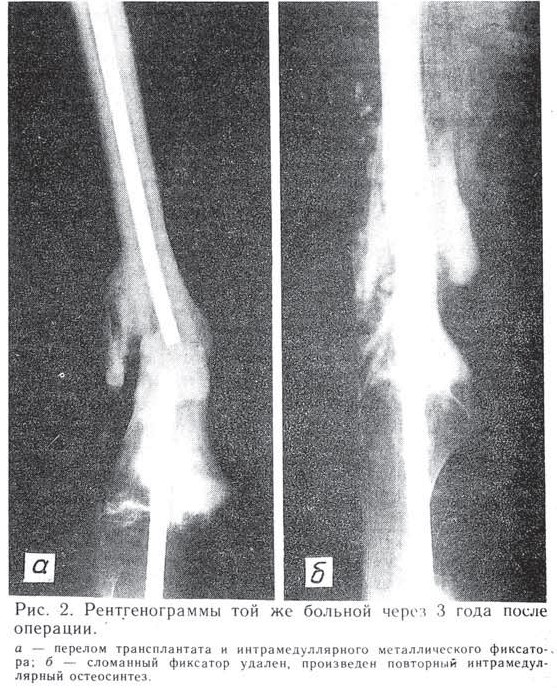

Рис.1 Рентгенограммы больной Д. до (а) и после операции (б)

Больная Д., 17 лет, оперирована 12.05.69 по поводу остеогенной саркомы дистального метаэпифиза правой бедренной кости. Произведены резекция дистального суставного конца бедренной кости, кипячение его в течение часа и реплантация с использованием массивного интрамедуллярного фиксатора типа НИИХАИ (рис. 1). Через 3 года возник перелом фиксатора и трансплантата (рис. 2, а), в связи с чем больная вновь оперирована: произведены удаление сломавшегося фиксатора и повторный интрамедуллярный остеосинтез (рис. 2, б). Постепенно произошла перестройка трансплантата, консолидация его на уровне перелома с большеберцовой костью. Больная вскоре вышла замуж и (вопреки нашим советам) родила двоих детей. Резкие гормональные перепады, связанные с беременностями и родами, не обострили течение заболевания. Через 24 года после операции здорова. Старшему сыну 20 лет.